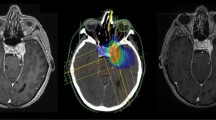

Outlining of the target and dose calculation was done in all patients using a HELAX TMS–treatment planning system (MDS Nordion, Ottawa, Canada). The clinical target volumes (CTV) were identified as being equal to the gross tumour volumes (GTV) and were defined close to the contour of the meningiomas on contrast-enhanced CT images. MRI scans were used as additional help in the target definition in many cases but only after year 2000 (Fig. 1a). The mean CTV in our material was 12.97 cm3 (Table 1). The planning target volume (PTV) was defined by adding a maximum margin of 5 mm around the CTV. Two or three proton-beam portals were applied (Fig. 1b). The aim was to keep all portals and their entrance doses in the same hemisphere as the targets. For centrally located targets though, it was more favourable to irradiate from both sides. All beams were given with passively scattered 180-MeV proton beams from a fixed horizontal beam using individually shaped collimators, range modifiers and modulating filters. The tumour dose was prescribed to the ICRU reference point located in a central part of the target volume (Fig. 1b) [28]. Care was taken to encircle the PTV with the 95% isodose according to the ICRU 50 protocol definition [28]. Dose limiting structures were considered to be the optic nerve, chiasm and brainstem where a maximum of 70% of the prescribed dose was allowed. In cases where the target was close to these structures, the target dose had to be compromised to meet the constraints. In accordance with our protocol, a total prescribed dose of 20 or 24 Gy was administered in four 5- or 6-Gy fractions, which corresponds approximately to an EQD2 (equivalent dose in 2-Gy fractions) of 43 Gy calculated with the linear quadratic formula [18]. The vast majority of the patients were treated according to the protocol with 5- or 6-Gy fractions (107 and 47 patients respectively). Fourteen patients were treated with various fractions between 3.5 to 4.5 Gy and the remaining two with 2-Gy fractions (Table 1).